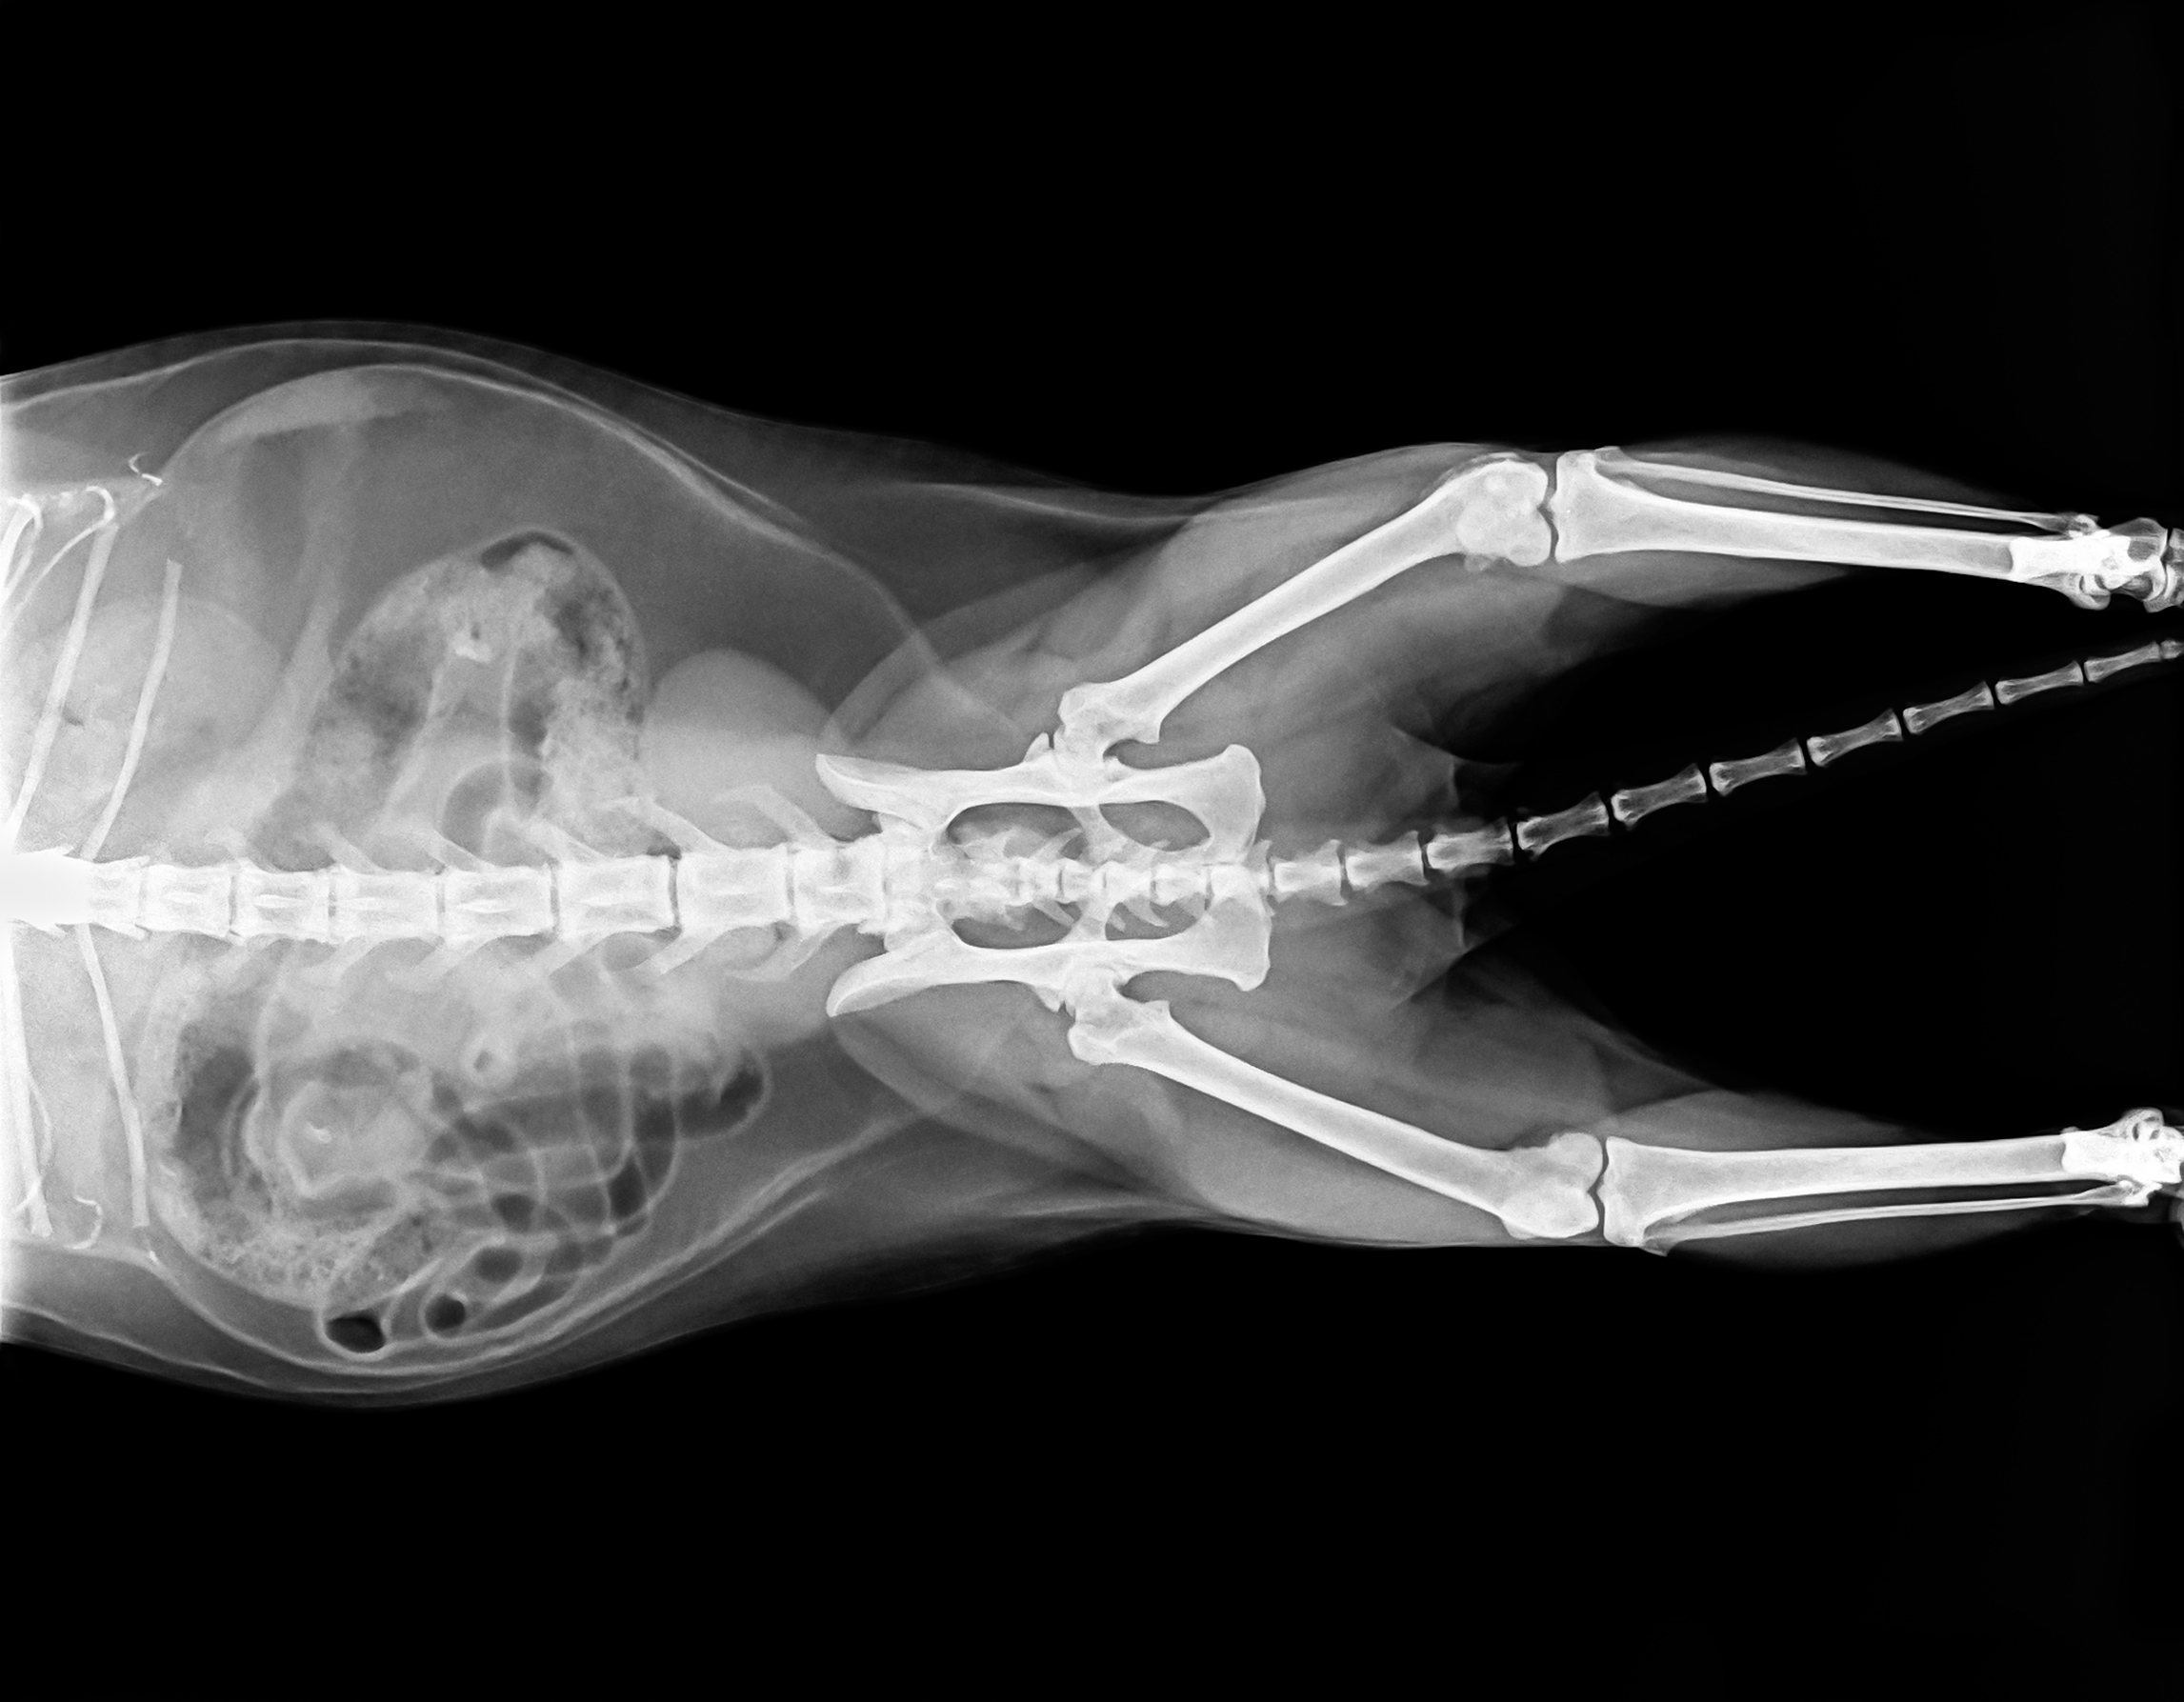

Рентгеновские снимки головы кошки в боковой проекции